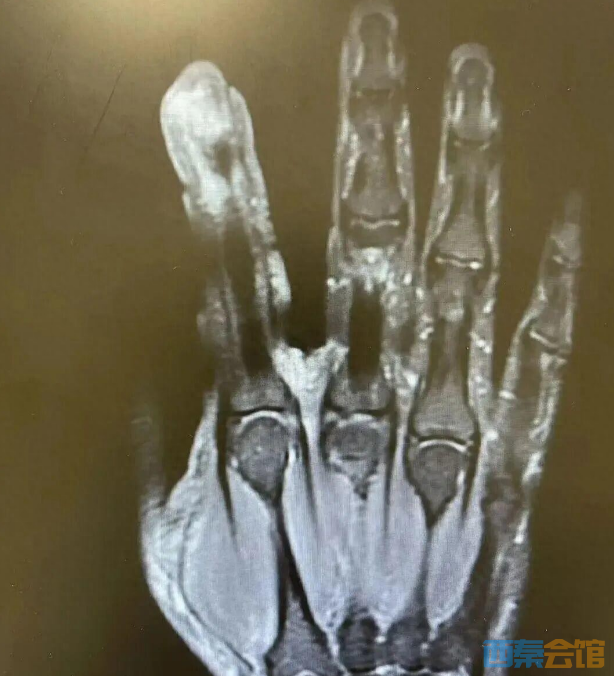

经检查,李大哥破溃的左手指尖严重感染,厌氧消化链球菌顺着破损处钻到骨头里,引发了严重骨髓炎。医生紧急手术,帮李大哥“刮掉”坏死的骨头碎片,清除了坏死的肌肉与皮肤。

医生表示。如果再晚一步,不仅手指保不住,还可能会引起脓毒血症,甚至危及生命。